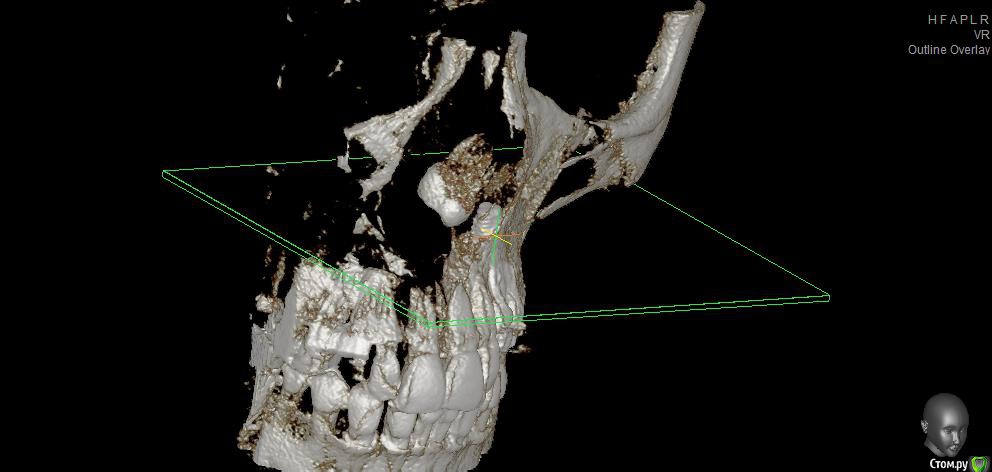

fifa888.dexo Опубликовано 22 июля, 2015 Автор Поделиться Опубликовано 22 июля, 2015 (изменено) Вот панорамный Изменено 22 июля, 2015 пользователем fifa888.dexo Ссылка на комментарий

fifa888.dexo Опубликовано 22 июля, 2015 Автор Поделиться Опубликовано 22 июля, 2015 а это все что я могла придумать с кт Ссылка на комментарий

diesel87 Опубликовано 22 июля, 2015 Поделиться Опубликовано 22 июля, 2015 По ОПТГ, формирователь не докручен, вам уже сказали, имплант в области левого клыка скорее всего не в контакте с четверкой (но надо глянуть КТ), даже если четверка депульпирована, она бы четко отреагировала бы на контакт с имплантом, болью или дискомфортом при накусывании/надавливании. В области синуса воспаление не особо просматривается и материал тоже четко не визуализируется в пазухе. Капать надо сосудосуживающее или гормональное. Выложите еще раз ссылку на КТ, ваши срезы не информативны. Ссылка на комментарий

diesel87 Опубликовано 22 июля, 2015 Поделиться Опубликовано 22 июля, 2015 http://fs2.directupload.net/images/150723/9sv48h7l.jpg http://fs1.directupload.net/images/150723/9nsd29hm.jpg http://fs2.directupload.net/images/150723/q4s456ou.jpg http://fs2.directupload.net/images/150723/9x7h27mc.jpg По КТ:1.возможно имплант в области клыка в апексе (самой верхней части) контактирует с четверкой (не ясно из-за того что имплант фонит), если четверка не реагирует, то пока наблюдать, делать прицельные снимки раз в 3/6/9/12 месяцев.2. Не докрученный формирователь, особо не страшно, но в щель может врасти десна, будет запах, локальное воспаление в области шейки импланта, так что лучше его докрутить или если он упирается в соседние зубы, поменять на узкий и докрутить.3. Имплант что в синусе, по снимку он практически весь в кости, а "воспаление" могло быть там и ранее, есть снимки до операции?? Ссылка на комментарий